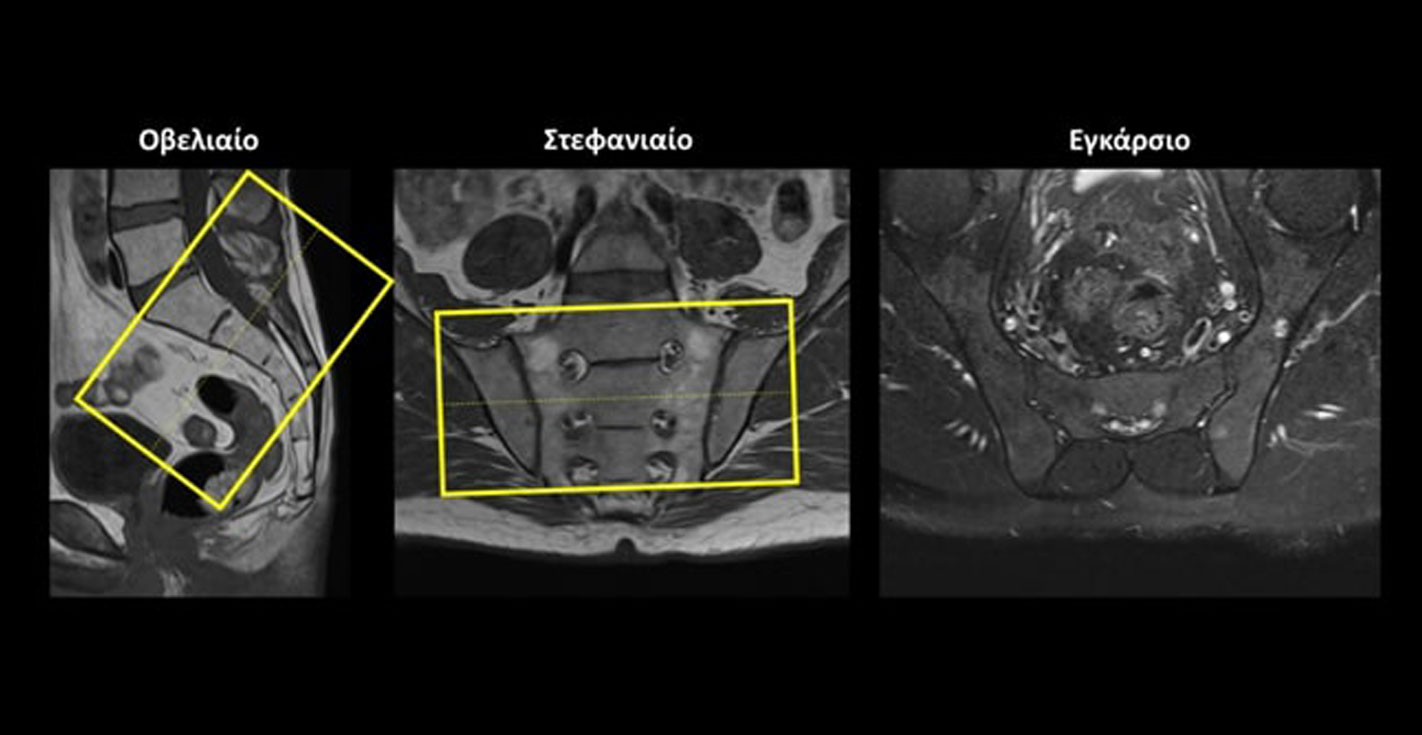

Στεφανιαίο (Coronal) ολόκληρης της πυέλου: οι στεφανιαίες τομές σχεδιάζονται παράλληλα με τις κεφαλές των μηριαίων στο εγκάρσιο επίπεδο και παράλληλα με την κατώτερη οσφυϊκή μοίρα της σπονδυλικής στήλης στο οβελιαίο επίπεδο. Οι τομές πρέπει να περιλαμβάνουν ολόκληρη την οστέινη πύελο, από την ηβική σύμφυση (μπροστά) έως το ιερό οστό (πίσω).

Εγκάρσιο (Axial/Transversal) στις ιερολαγόνιες αρθρώσεις: οι εγκάρσιες τομές σχεδιάζονται κάθετα στον Ι2 σπόνδυλο στο οβελιαίο επίπεδο και παράλληλα με τη νοητή γραμμή που ενώνει τις ιερολαγόνιες αρθρώσεις στο στεφανιαίο επίπεδο. Οι τομές πρέπει να περιλαμβάνουν ολόκληρες τις ιερολαγόνιες αρθρώσεις.

Στεφανιαίο (Coronal) στις ιερολαγόνιες αρθρώσεις: οι στεφανιαίες τομές σχεδιάζονται παράλληλα με τον Ι2 σπόνδυλοστο οβελιαίο επίπεδο και παράλληλα με τη νοητή γραμμή που ενώνει τις ιερολαγόνιες αρθρώσεις στο εγκάρσιο επίπεδο. Οι τομές πρέπει να περιλαμβάνουν ολόκληρες τις ιερολαγόνιες αρθρώσεις.